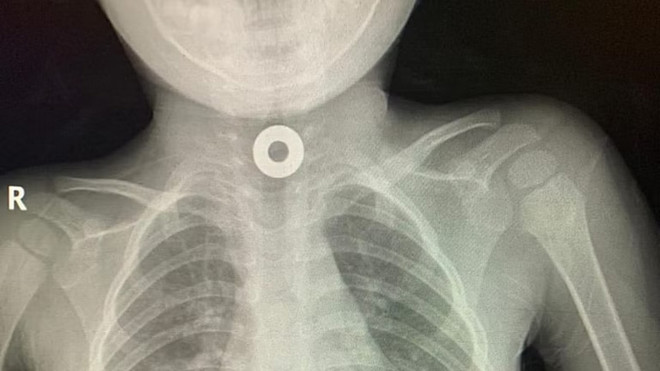

طائف میں ڈاکٹروں نے بچے کے حلق سے دھاتی نٹ نکال لیا

بچے کی حالت بہتر ہونے کے بعد اسے ہسپتال سے فارغ کردیا گیا۔ (فوٹو سبق)

طائف میں کنگ عبدالعزیز سپیشلسٹ ہسپتال کے ڈاکٹروں نے دھاتی نٹ نگلنے والے دو سالہ بچے کی زندگی بچالی۔

محکمہ صحت کا کہنا ہے کہ بچے کی صحت صورتحال اور ایکسرے کرانے  کے بعد پتہ چلا کہ بچہ کوئی ایسی چیز نگلے ہوئے ہے جس کی شکل دھاتی نٹ جیسی ہے۔